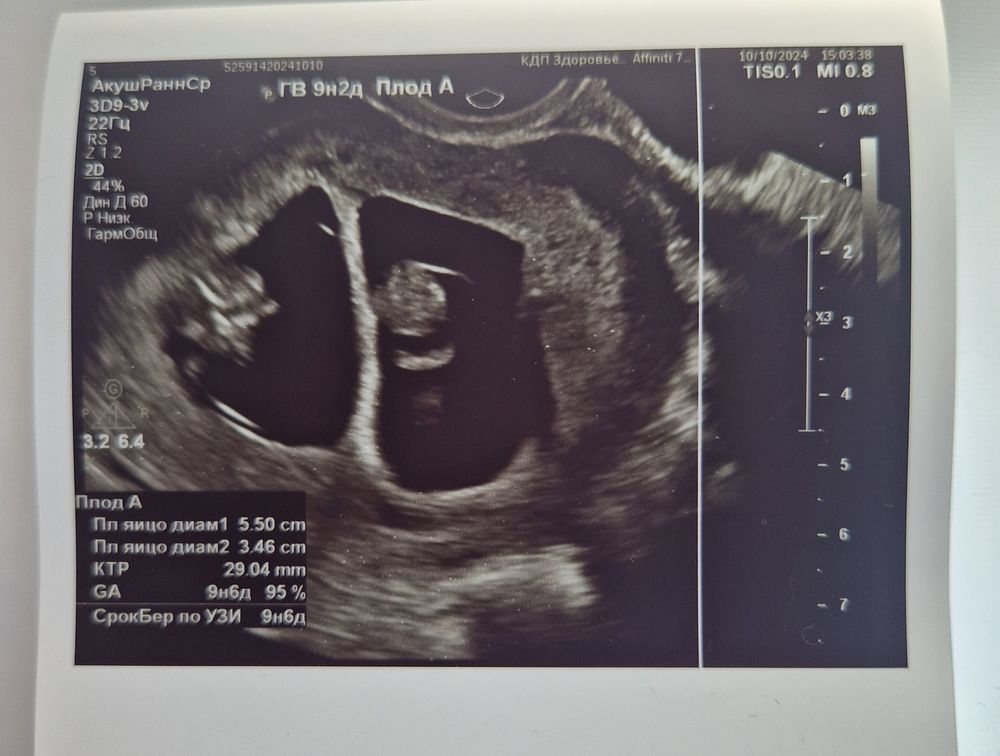

Дарина в Зачатие год Покидайте фото узи в 9 недель 🙏🏻 УЗИ Девочки у кого остались или есть фоточки покидайте пожалуйста! Хочу сходить в 9 неделек на узи, с монитором, хочется узнать как что там примерно видно будет Посмотрите еще 20 записей на эту тему Лучший ответ Елена 9н 2д двойня 02.11.2024 Ответить Отменить Ответить Таня Орозова 01.11.2024 Ответить Екатерина 01.11.2024 Ответить Екатерина Екатерина, чуть больше, 9,5 01.11.2024 Ответить Евгения 9+3 недели 01.11.2024 Ответить ЛисАлис 01.11.2024 Ответить Екатерина 01.11.2024 Ответить Екатерина Екатерина, 9 недель ровно, первое УЗИ 01.11.2024 Ответить Екатерина Екатерина, ножки попка к верху 😄 01.11.2024 Ответить Дарья 01.11.2024 Ответить Евгения Дарья , а вам делали трансвагинально или абдоминально? 01.11.2024 Ответить Дарья Евгения, трансвагинально . А вот 10 недель узи) 01.11.2024 Ответить Евгения Дарья , ух ты) а мне абдоминально делали😁 как в этот раз будут не знаю, пойду в другое место 01.11.2024 Ответить Евгения 01.11.2024 Ответить Мира В интернете нашла)) 01.11.2024 Ответить Девочки подскажите !! Пост нытья Чаты Беременных Выберите чат: Январята-2026 Февралята-2026 Мартята-2026 Апрелята-2026 Майчата-2026 Июнята-2026 Июлята-2026 Августята-2026